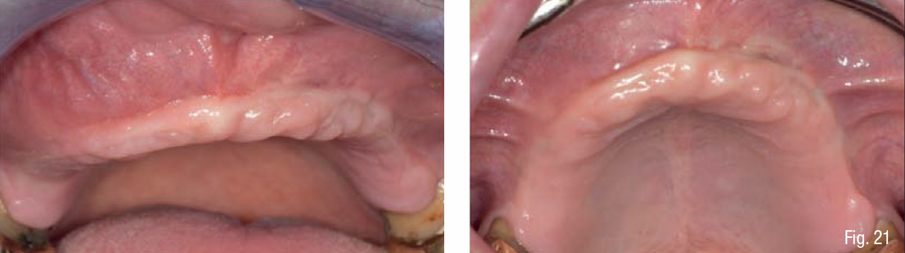

Un paziente di 65 anni, ASA-2, non fumatore è giunto alla nostra osservazione presentando un’edentulia quasi totale del mascellare superiore, con persistenza soltanto dei primi molari 16 e 26 a supporto di una protesi parziale rimovibile, una severa perdita di dimensione verticale occlusale, e una conseguente terza classe acquisita (Fig. 1). La richiesta del paziente era la risoluzione dell’edentulia con protesi fissa supportata da impianti che gli restituisse una funzione e un’estetica ottimale del mascellare superiore ed era già a conoscenza delle problematiche relativa alla mancanza di osso e della necessità di una ricostruzione ossea prima del posizionamento implantare.

Gli esami radiologici di primo livello, quali la OPT, evidenziavano un’altezza ossea sufficiente al posizionamento implantare, ma la successiva analisi di secondo livello, quale la CBCT, evidenziava la presenza di una grave atrofia orizzontale a livello della regione edentula che rendeva impossibile la chirurgia implantare, oltre ad un quadro di sinusite mascellare cronica bilaterale. Su richiesta del paziente, si è deciso di mantenere i 2 molari sup. che sono stati trattati endodonticamente e successivamente protesizzati con 2 corone in zirconia; e di non eseguire il rialzo di seno mascellare bilaterale evitando l’iter terapeutico di approfondimento ORL.